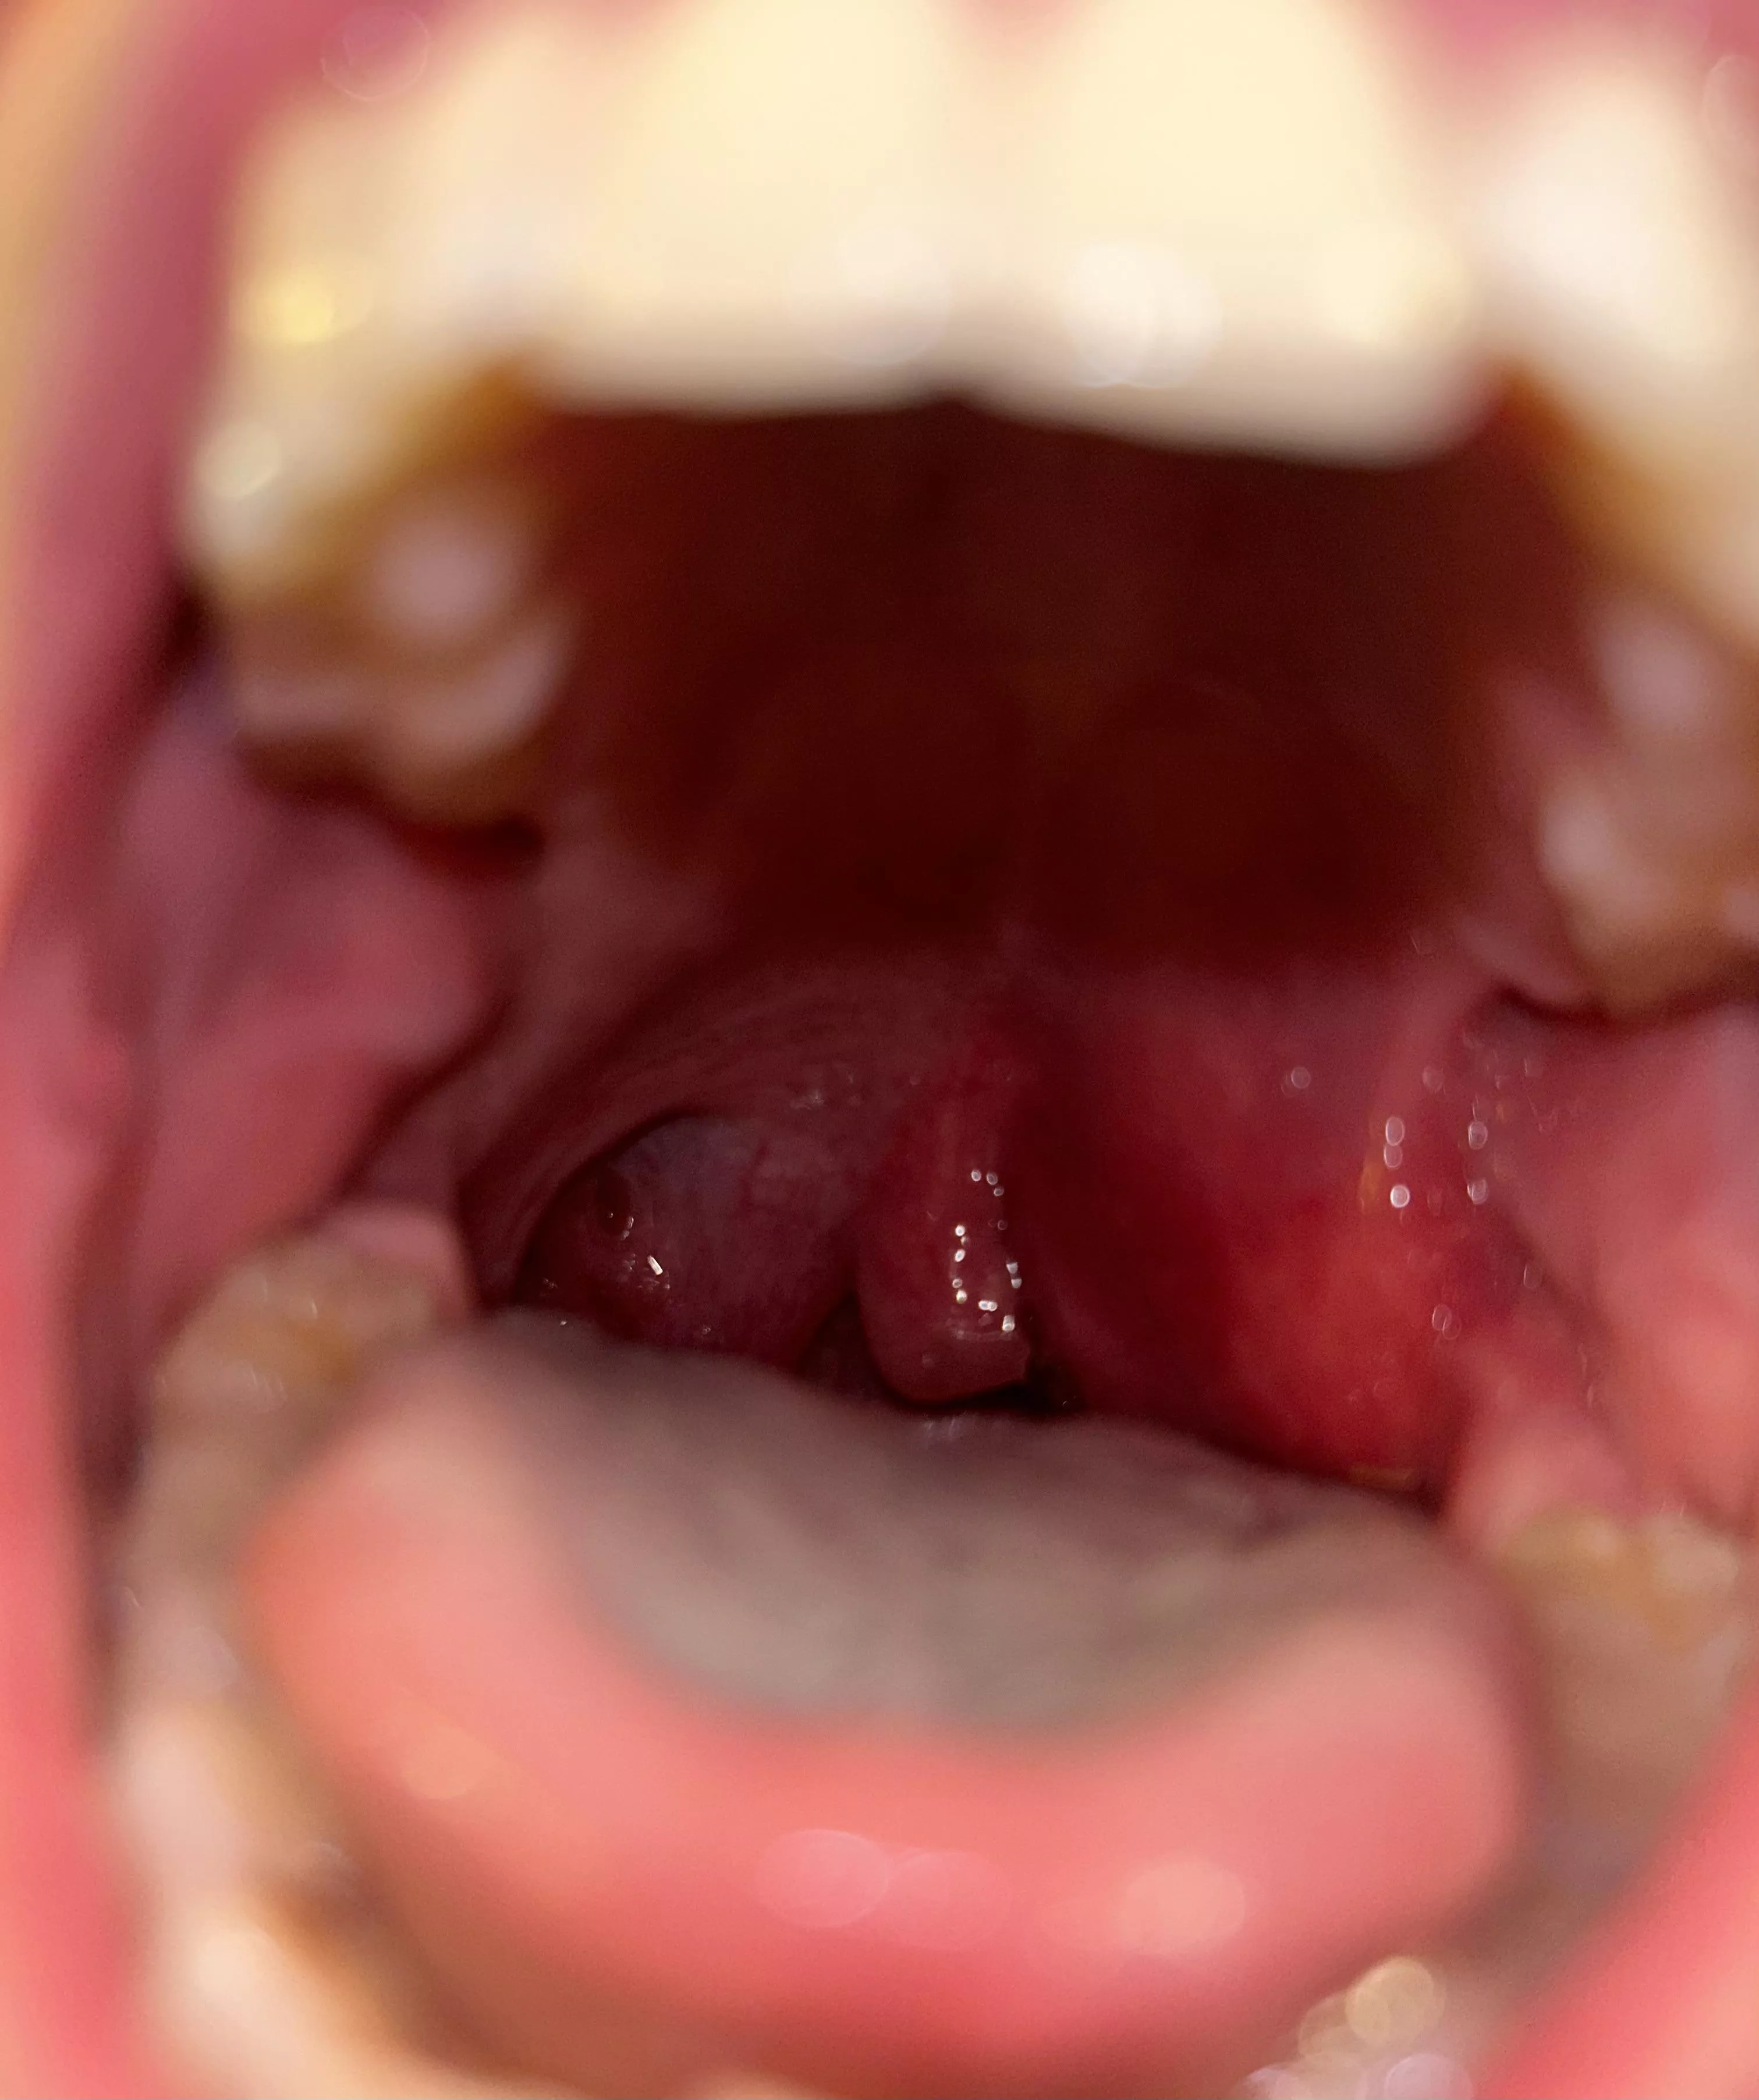

Quinsy before it burst at home. Extremely painful and scary.